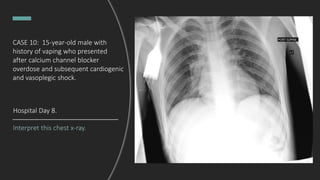

CASE 10: 15-year-old male with

What do you see?

Endotracheal tube in good position.

Hazy perihilar opacities.

DDx: pulmonary edema, aspiration

pneumonia

Interpret this chest x-ray.

Hospital Day 8.

Interval extubation and removal

of chest tube. No pneumothorax.

No recurrent effusion. Clear lungs.

Final Dx: MRSA pneumonia

with parapneumonic effusion.